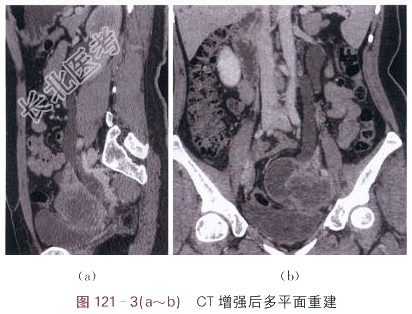

- [材料题] 患者,女,44岁,发现腹部包块2月余。体格检查:未见阳性体征。影像学资料如图121-1~图121-3所示。

- 简答题1、请叙述卵巢癌临床症状和该影像学表现?